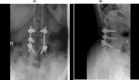

Figure 7

(A, B) Anteroposterior and lateral postoperative x-rays, respectively, showing 2 rods and transpedicular screws seen transfixing the vertebral body from L2 to L4. No evidence of looseness or alignment deformity. There is no pedicle screw on the left L3 vertebra.

Figure 8

(A, B) Anteroposterior and lateral views of follow-up x-rays, respectively, 2 years postoperatively showing 22 rods and transpedicular screws seen transfixing the vertebral body from L2 to L4. No evidence of looseness or alignment deformity. There is no pedicle screw on the left L3 vertebra.